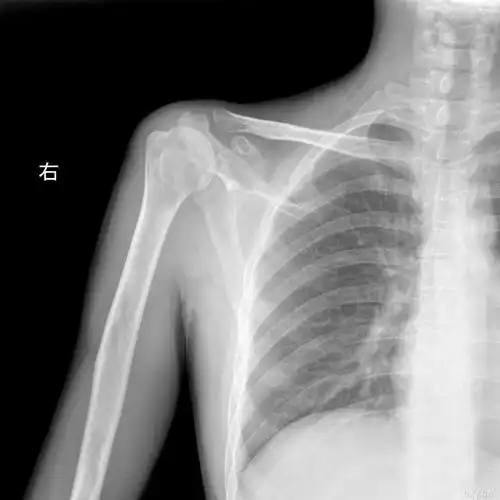

【讨论】右肩胛骨病变(20060207)